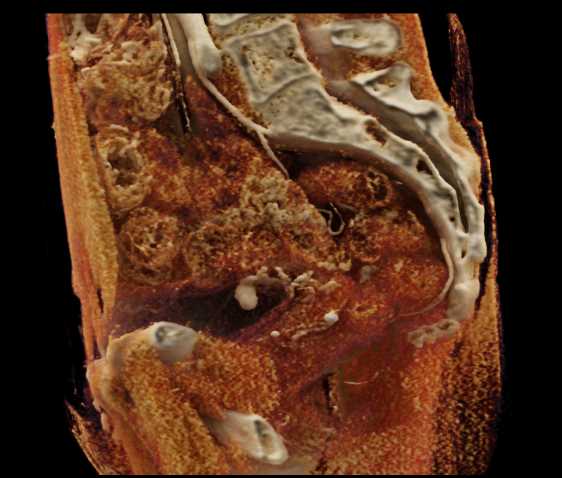

Urachal Carcinoma of the Bladder